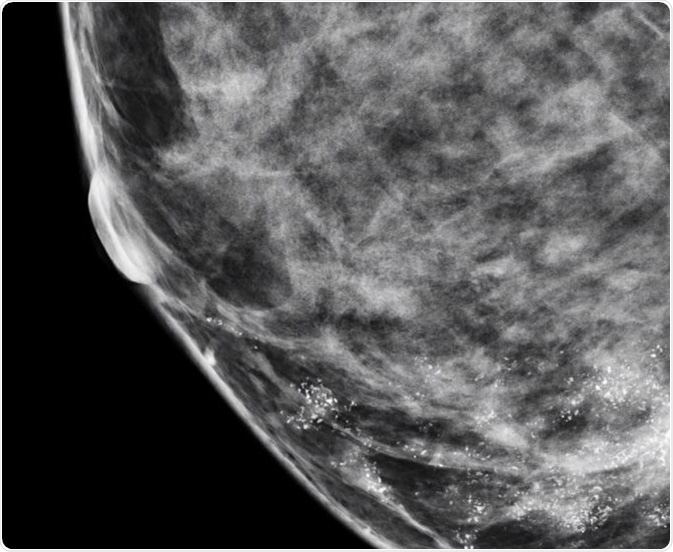

Calcifications in the breast can be benign or malignant. They can appear as either macrocalcifications or microcalcifications on a mammogram (i.e. an X-ray of the breast). Macrocalcifications look like large white dashes or dots and are mostly noncancerous and no further tests are required usually.

Microcalcifications are actually calcium deposits and are seen as tiny, white dots on a mammogram. They are much less common and are mostly a result of mutations in the breast tissue, though they can be caused by other factors. The appearance of microcalcifications is widely used in the detection of breast cancer at an early stage and can lead to better outcomes.

Nearly 50% of non-palpable cancers in the breast are detected only by the presence of microcalcifications on a mammogram, and approximately 93% of people with ductal carcinoma in situ (DCIS) also present with microcalcifications. Microcalcifications in the breast are very common in women and some studies have observed significant variations in the elemental composition of benign and malignant calcifications.

In general, when the distribution of microcalcifications is diffuse or bilateral, when they have a round and/or punctuate shape, or when they are scattered in the breast tissue, the condition is usually benign. On the other hand, if microcalcifications have a linear or branching pattern with irregular borders, or if they have variable density, or when they are distributed in a haphazard or segmental way, there is a high probability that it is ductal carcinoma in situ or malignant cancer.

The nature of microcalcifications cannot always lead to a conclusive diagnosis and in such cases they are said to be ‘suspicious‘ – thus, a biopsy is required to confirm the benign or malignant nature of the cancer. If the distribution of the microcalcifications is linear and they are in round, oval, or amorphous form, they are termed as ‘suspicious’.

Radiologists usually term a variable distribution density where the breast microcalcifications are closely packed at one place and widely spread at another as ‘suspicious’, and not definitive, for cancer. It is referred to as ‘cluster of suspicious-looking microcalcifications0 on a mammogram report.